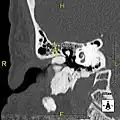

Normal ear canal

Exostosis in ear canal

The normal ear canal is approximately 7 mm in diameter and has a volume of approximately 0.8 ml (approximately one-sixth of a teaspoon).[5] As the condition progresses, the diameter narrows and can even close completely if untreated, although people generally seek help once the passage has constricted to 0.5–2 mm due to the noticeable hearing impairment. While not necessarily harmful in and of itself, constriction of the ear canal from these growths can trap debris, leading to painful and difficult to treat infections.